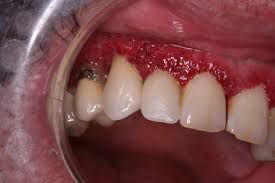

What is strawberry gingivitis?

Hyperplastic gingival lesions or strawberry gingivitis, is a characteristic sign of Wegener's granulomatosis. The latter consists of reddish-purple exophytic gingival swellings with petechial haemorrhages thus resembling strawberries.